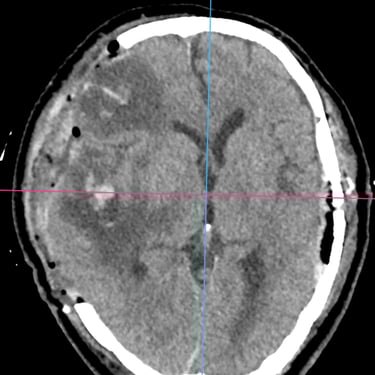

TEC Severo: Craneotomía Descompresiva Hemisférica y Evacuación de Hematoma Extradural

El traumatismo encéfalo craneano (TEC) severo es una emergencia neurológica que puede comprometer rápidamente la vida del paciente. Cuando existe edema cerebral difuso y hematomas asociados, el tratamiento quirúrgico oportuno es fundamental. La craneotomía descompresiva hemisférica derecha permite reducir la presión intracraneal y prevenir daño cerebral secundario, mientras que la craneotomía temporal izquierda con evacuación de hematoma extradural (HED) elimina el efecto de masa local. Este abordaje combinado busca preservar la perfusión cerebral, estabilizar al paciente y mejorar el pronóstico neurológico en situaciones críticas.